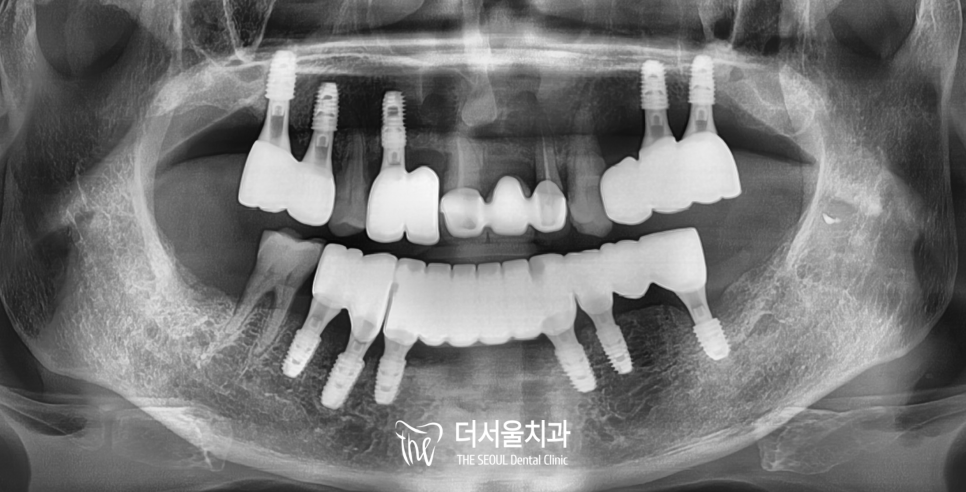

일정 기간을 거쳐

픽스처가 단단하게 유착된 결과를 확인한 후

정교하게 제작된 보철을 올려드리며

치료가 마무리되었습니다.